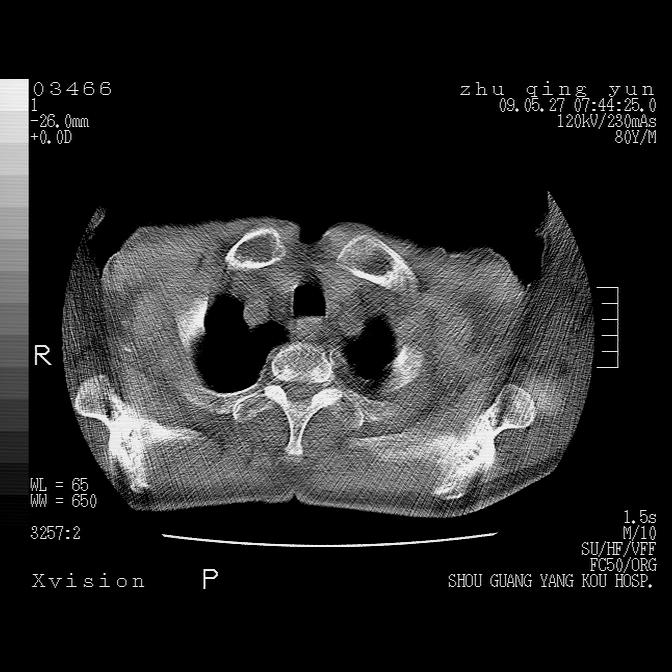

病人男性,年龄80,气喘来院,其他病史不太详细,1月前有过恶心,呕吐,在当地人民医院做过钡餐,诊断胃炎,

1)考虑左肺中央型肺癌并阻塞性肺炎,后下纵隔受侵伴纵隔淋巴结转移。2)双侧少量胸腔积液,胸膜增厚。3)心包积液。

双侧胸腔积液。